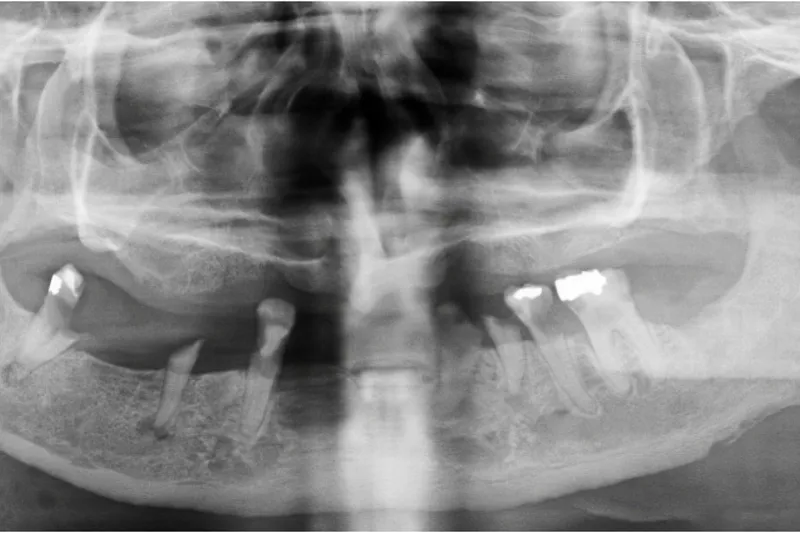

Nekrotiserende bløddelsinfektioner i hoved-halsområdet er en sjælden, aggressiv tilstand med høj dødelighed. Infektionen breder sig ud i alle blødtvævslag forårsagende iskæmi og nekroser. Tilstanden kræver hurtig diagnostik og akut kirurgisk sanering for at indskrænke infektionens udbredelse og undgå tab af væv og funktioner. Den nationale vejledning for visitation og behandling af disse patienter foreskriver, at patienterne overflyttes til regionshospitaler, hvor alle kirurgiske specialer er til rådighed. For overflytning til Region Hovedstaden anvendes der også adjuverende hyperbar iltbehandling forudgået af understøttende intensiv behandling, kirurgiske saneringer, bredspektret antibiotikum, og i udvalgte tilfælde behandling med immunglobulin. Data viser, at halvdelen af alle patienter med nekrotiserende bløddelsinfektion i hoved-hals-området udgår fra et odontogent fokus – størstedelen fra mandiblens molarregion. De resterende nekrotiserende hoved-hals-infektioner udgår fra tonsiller, svælg- og strubeinfektioner samt efter kirurgiske indgreb. Infektionen viser sig ofte ved bløddelshævelse på halsen og perimandibulært, der kan være misfarvninger af huden, og patienterne har stærke smerter sv.t. det afficerede område. Patienterne udvikler sepsis og nogle septisk shock. Årsagen til, at nogle patienter udvikler nekrotiserende infektion, er stadig ukendt.

• Halvdelen af de nekrotiserende bløddelsinfektioner i hoved-hals-området udgår fra et tandfokus – ofte efter et nyligt tandindgreb eller grundet dårlig tandstatus.